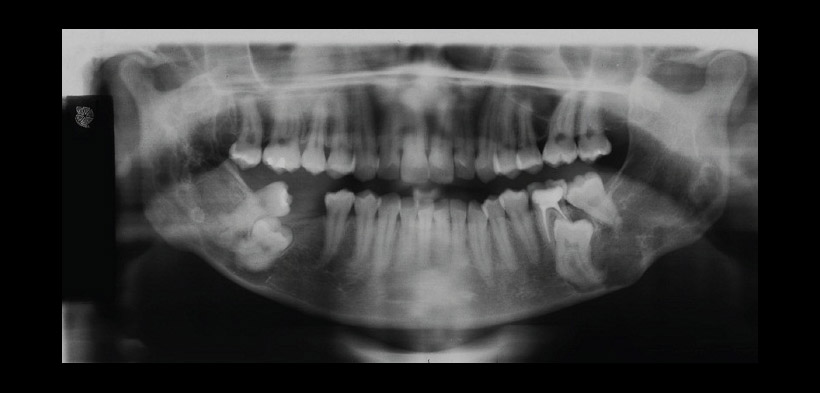

Fig. 1 Radiografía panorámica de una paciente femenina de 18 años, que muestra el crecimiento bilateral de la lesión en el cuerpo, rama, y las apófisis coronoides de la mandíbula, produce la erupción atípica de los terceros molares inferiores, y la reabsorción de la raíz distal del primer molar inferior izquierdo.